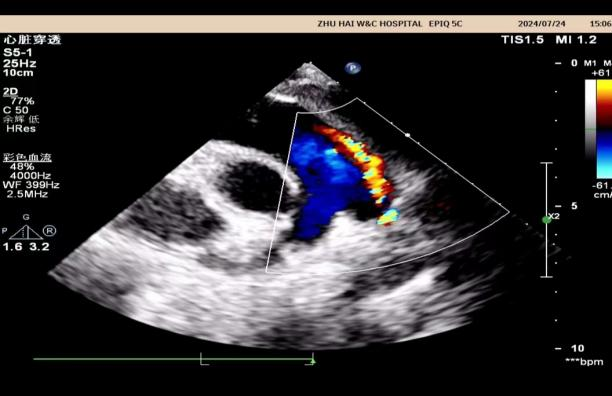

心脏彩超是能够动态显示心腔内部结构、心脏搏动和血液流动情况的一种无创性检查技术。通俗地说,心脏探头有点类似于摄像机的镜头,通过镜头的不断移动和变换,让心脏的各个结构得到准确的呈现,从而让医生能够根据这些图像判断心脏是否存在问题。

心脏彩超除了对于先天性心脏病有比较好的显示效果外,对于后天因素所导致的心脏病,同样能够有很好的诊断效果。比如常见的瓣膜狭窄、瓣膜关闭不全、风湿性心脏瓣膜病、冠心病、肥厚型心肌病、扩张性心脏病等。

比如心包积液,可以评估心包积液的多少,了解有没有心包钙化、心包增厚等。对于心脏临近结构如主动脉、肺动脉可以直观显示,了解这些大血管有没有病变。